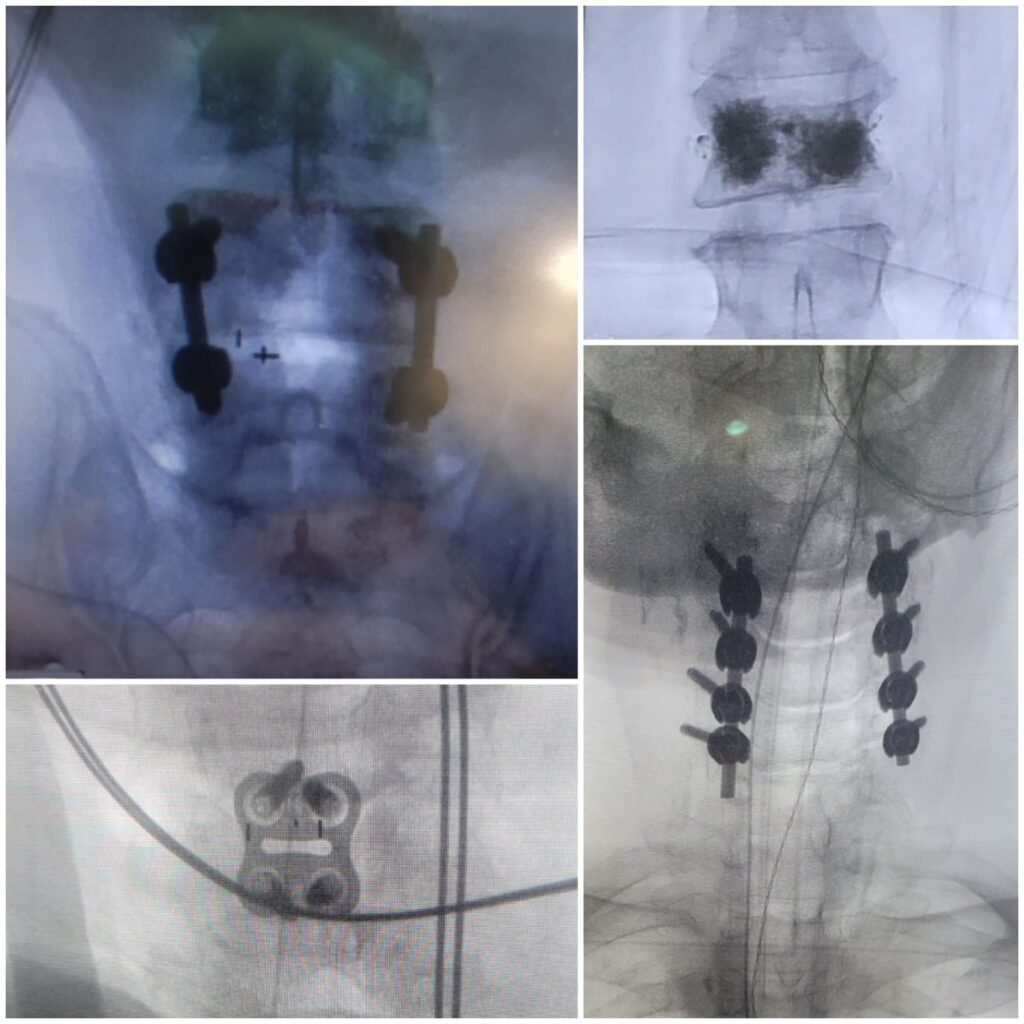

Trimaco Medical & Surgical is a leading Israeli supplier and distributor of advanced medical devices for hospitals and clinics. The company specializes in surgical technologies and provides comprehensive technical and clinical support, working closely with medical teams, hospital management, and international manufacturers. Trimaco represents innovative medical solutions across multiple high-impact clinical fields, with a strong emphasis on quality, regulatory compliance, and long-term partnerships.

OUR EXPERTISE